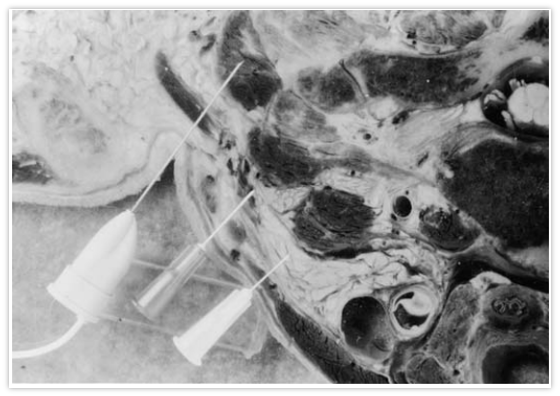

Deep Layers

Splenius Capitis

Splenius Cervicis

Semispinalis Capitis

Semispinalis Cervicis

Layer 1

Layer 2

Layer 3